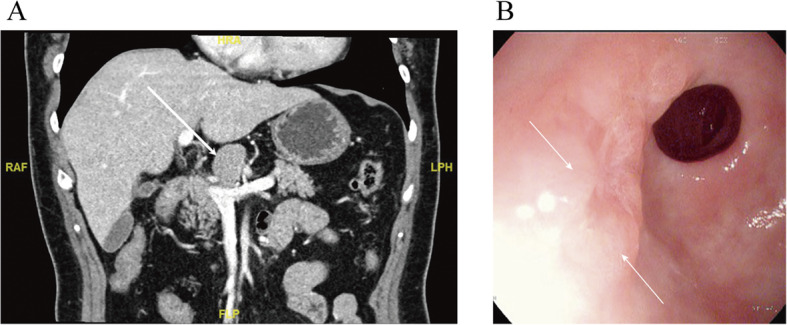

Fig. 2.

The last preoperative tests. a The latest contrast-enhanced abdominal CT. Stable solitary nodule (32 mm × 25 mm), labeled by the white arrow, without other abnormal findings. b The retaken gastroscopy found two bumps with mucosa erosion near the pylorus on the anterior gastric antrum, and a biopsy was taken around this area

An endoscopic ultrasonography-guided puncture was performed, and biopsy found suspicious adenocarcinoma cells unexpectedly (Fig. 3). At the same time, a random biopsy of the two bumps with mucosa erosion near the pylorus on the anterior gastric antrum and pyloric mucosa revealed high-grade intraepithelial neoplasia, while gastroscopy showed normal appearance of the other gastric mucosae (Fig. 2b).